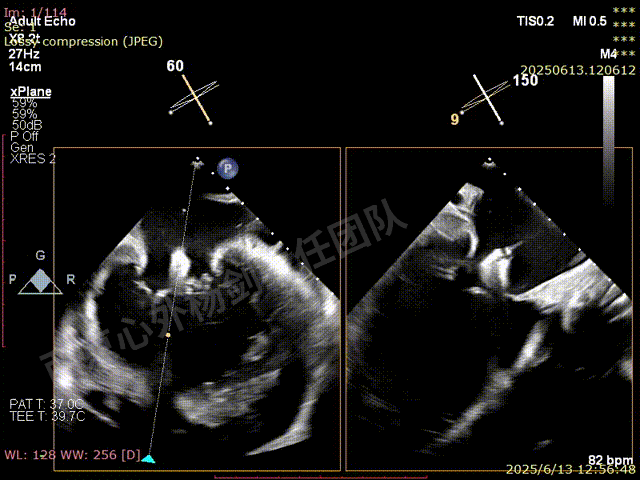

第一枚XTW在2区弹道测试调整

第一枚XTW打开确认orientation,穿刺位置良好无需调整hug

XTW进入瓣下,以较小的角度先捕捞后叶

反复尝试,瓣叶卷曲,前后瓣叶不明确

捕捞完成后确认orientation,gripper down